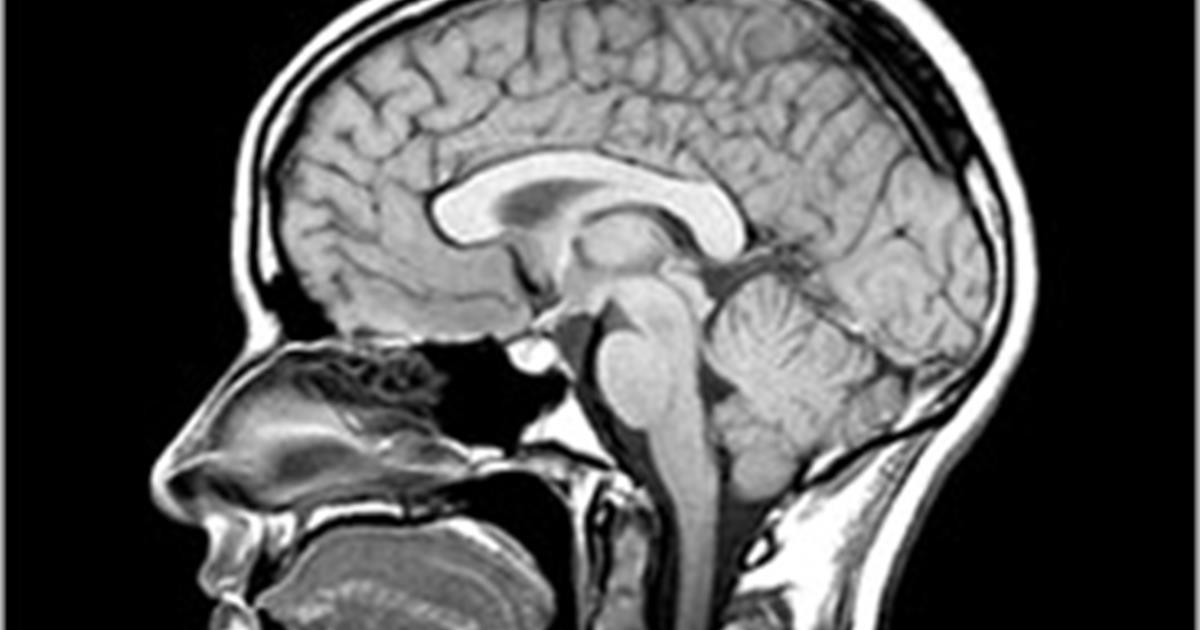

is this a CT or MRI image